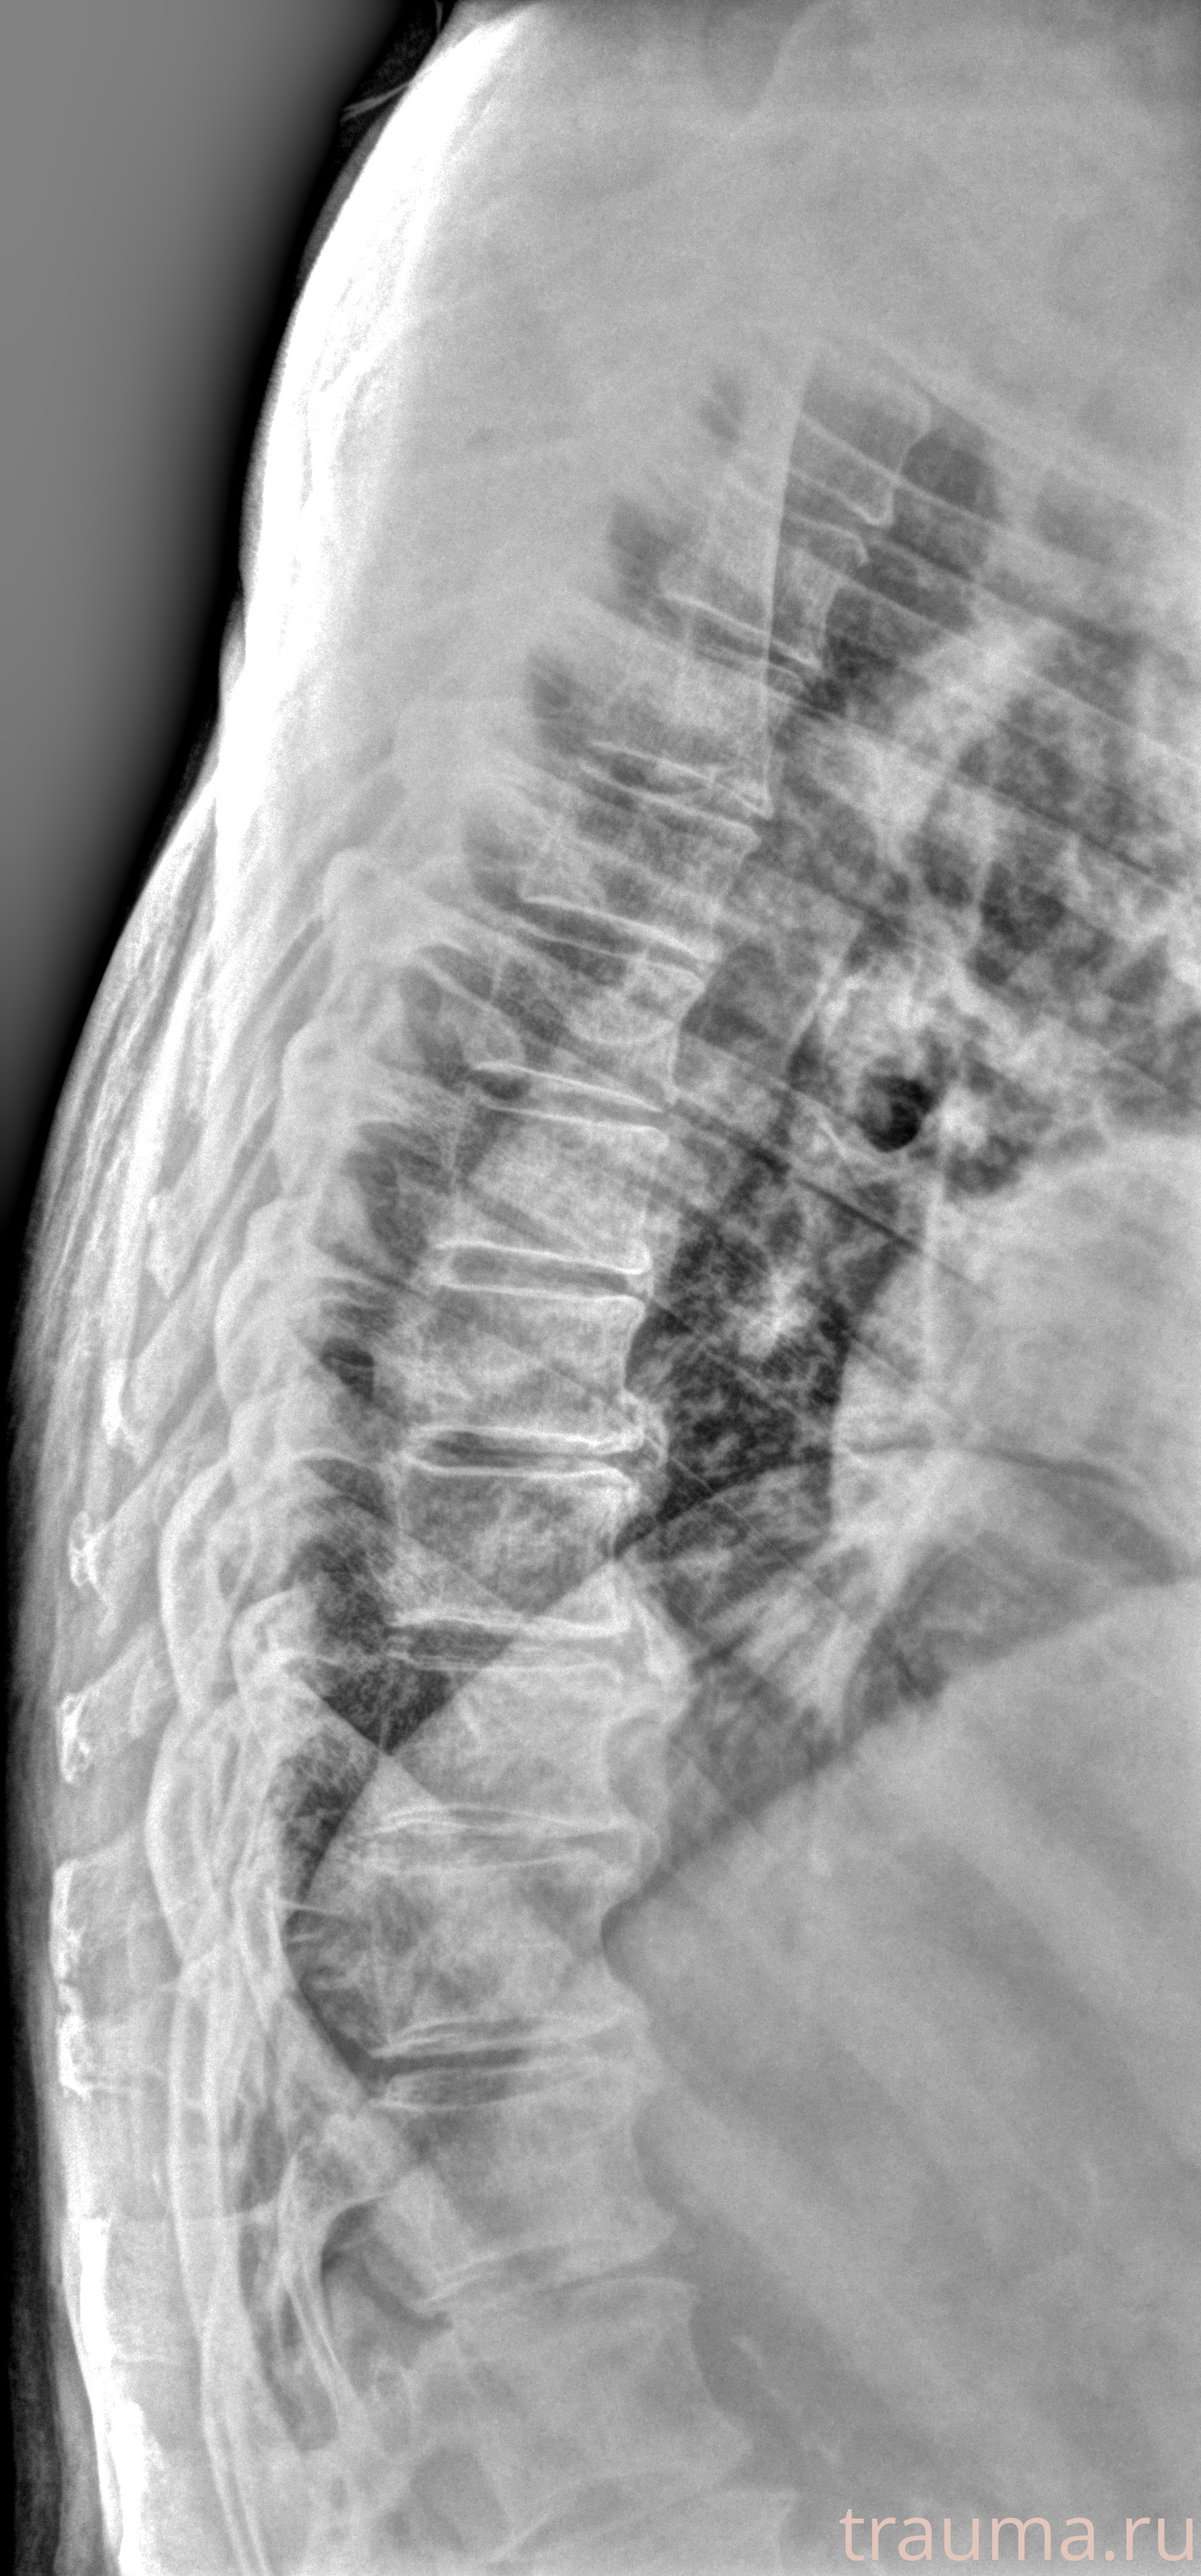

Рентгенограммы

Рентген на дому: по вашему адресу приезжает врач-рентгенолог, травматолог-ортопед с мобильным рентгеновским аппаратом, проводит диагностику травмы или заболевания, делает необходимые рентгенограммы, дает рекомендации по дальнейшему лечению. Получить качественные снимки в домашних условиях возможно благодаря уникальной методике, разработанной МосРентген Центром для института  Склифосовского